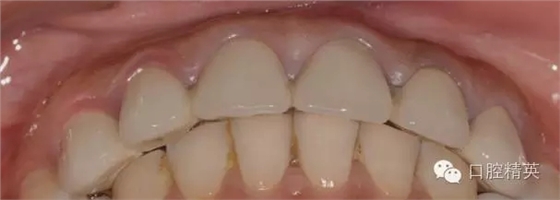

患者發(fā)F音以及下嘴唇干濕線的位置

修復體完成口內(nèi)照片